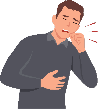

MECHANISM OF ACTIONS (MOA)

EA 575® is also unique to help improve respiratory function in patients with bronchitis.

- The EA 575® is an active ingredient from natural ivy leaf which liquefies the sticky mucus trapped in the air passages of the lungs.

- It then acts as an expectorant, allowing the mucus to be coughed up more easily.

- As the air passages relax and widen, you are able to breathe better and more comfortably.